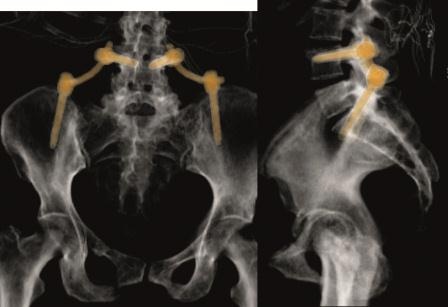

Sakrummetastasen: Stabilitätsgefährdende Metastasen am Sakrum (Abb. 3a) und am hinteren Beckenring werden zumeist mit einer mono- oder bilateralen vertebropelvinen Abstützung versorgt (Abb. 3b). Insbesondere das Os sacrum kann so aus der lasttragenden Kette herausgenommen werden. Vor allem bei Mammakarzinommetastasen kann mit der nachfolgenden Radiatio häufig eine so stabile Rekalzifikation erzielt werden (Abb. 3c), dass mitunter bei Beschwerden über dem Fixateur besonders bei schlanken Patienten eine Metallentfernung erwogen werden kann. Sollte das dorsale Os ileum mit betroffen sein (Abb. 4a) kann bei entsprechenden anatomischen Voraussetzung (Abb. 4b) auch weiter ventral auf den Beckenkamm abgestützt werden (Abb. 4c).